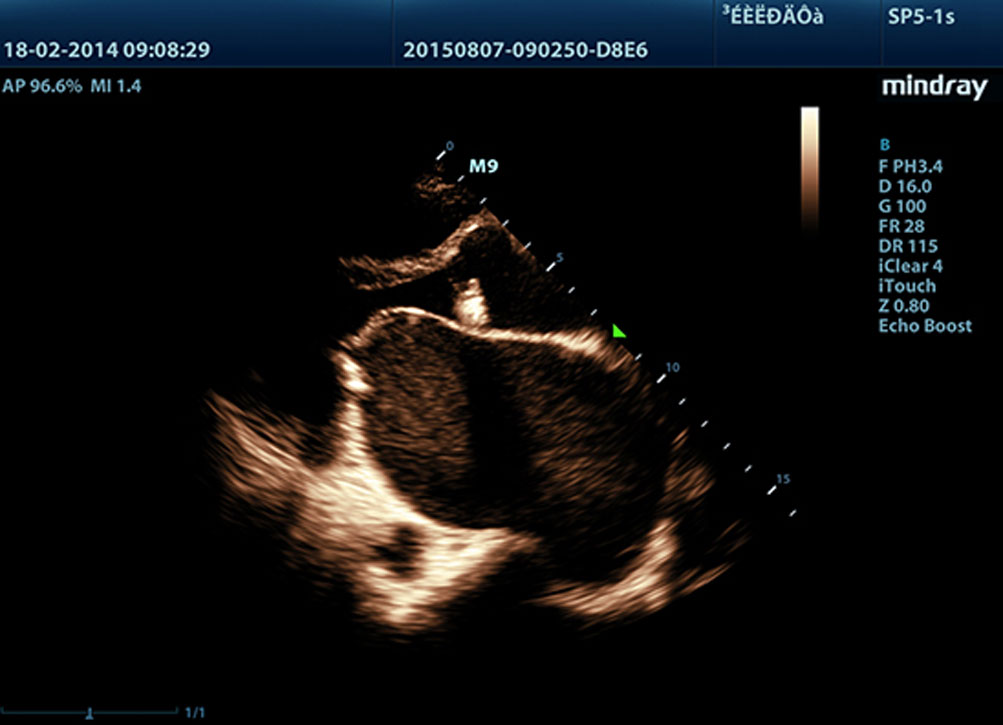

?? ?????? ?? LVO

M9? ???? ??? ?? ?? LV ????? ?? ?? ??? ?? ? ?? ??? ???? ??? ??? ?? ?? ???? ?????. M9? ?? ????? ??? ???? ??? ?? ?? ??? ?? ??? ???? ?????. ? ???? ???? ??? ?? ???? ? ?? ??? ?? ?? ???? ?? ?????.